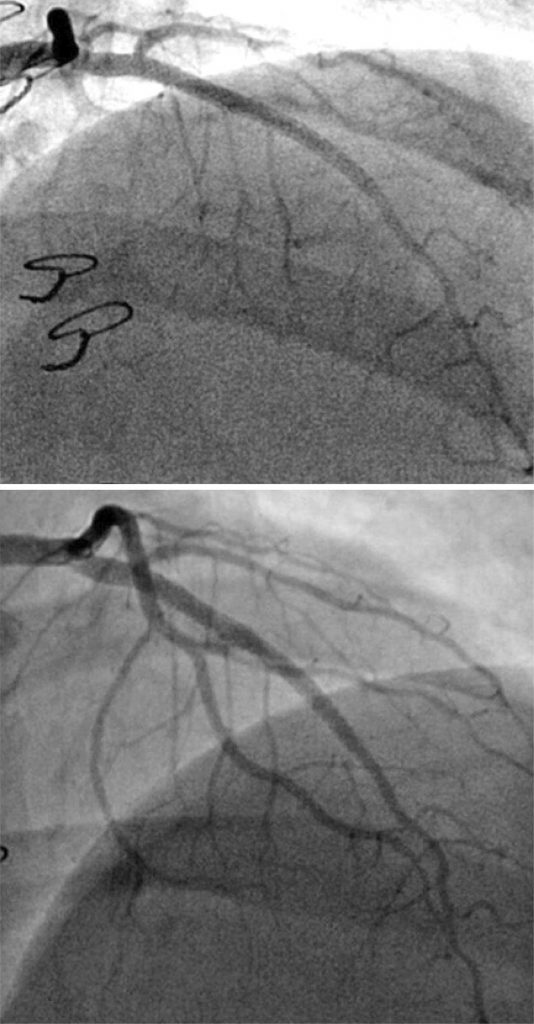

Figure 4

Final coronary angiography and 3-month follow-up coronary angiography